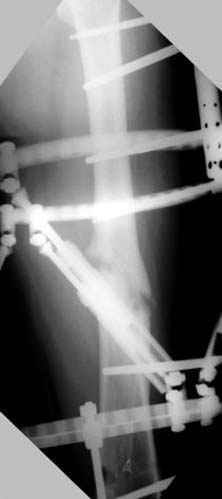

Несколько снимков из моей коллекции, чтобы разьяснить, почему мы до сих пор делаем различные варианты остеотомии.

На рисунке N1 предоперационный план лечения ложного сустава шейки бедра- линия ложного сустава, угол и направление введения импланта, клиновидная остеотомия в градусах и миллиметрах, второй снимок после коррекции, расчет, на сколько удлиняется конечность и размеры импланта;

N3 рисунок окончательный снимок, после операции моя рентгенограмма должен выглядеть примерно как эта картина. На N4 снимке клин перед удалением; N5 послеоперации 3 нед.; N6 окончательная рентгенограмма.

пластическая модель; и коррекция бедра аппаратом Илизарова.